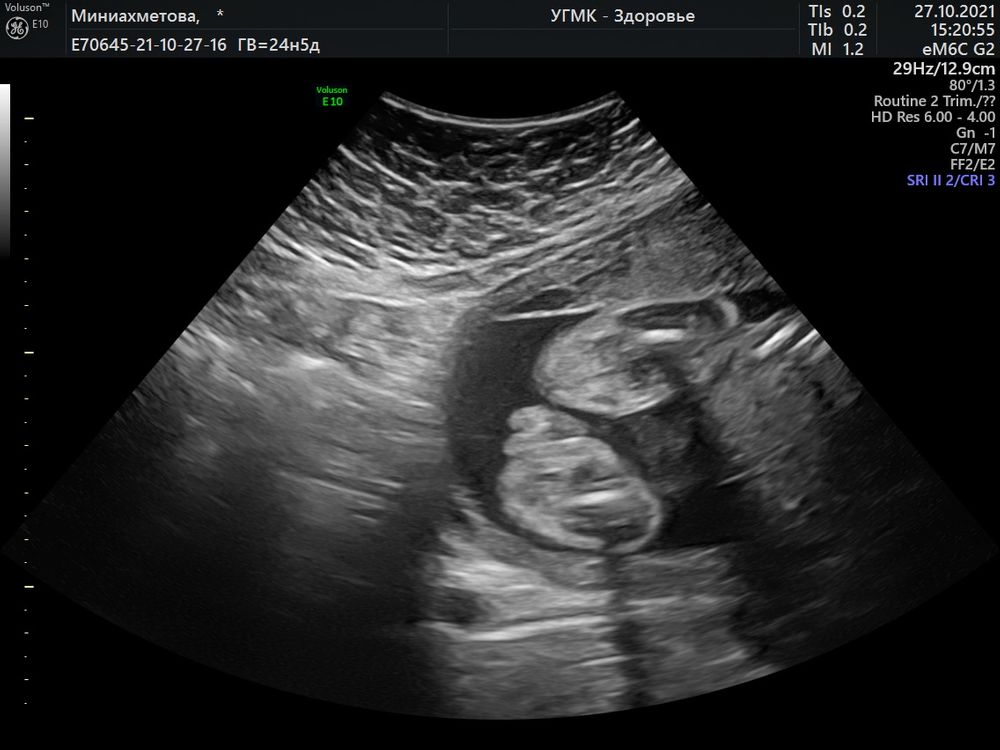

Пол малышаВсем привет.У нас головоломка 🧩 Сказали на узи девочка,но никак не понимаем как же могут быть губешки со стороны спины.Как

думаете,мальчик или девочка?

Это пузико, а не спина. И ножки поджаты и хорошо так продемонстрировала что она малышка😊